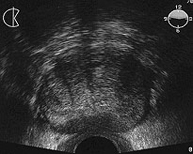

Ecografía. Sirve para conocer el tamaño exacto y el peso de la glándula prostática, indica el estado de la vejiga urinaria y nos orienta sobre el grado de dificultad para la micción que puede causar una próstata agrandada.